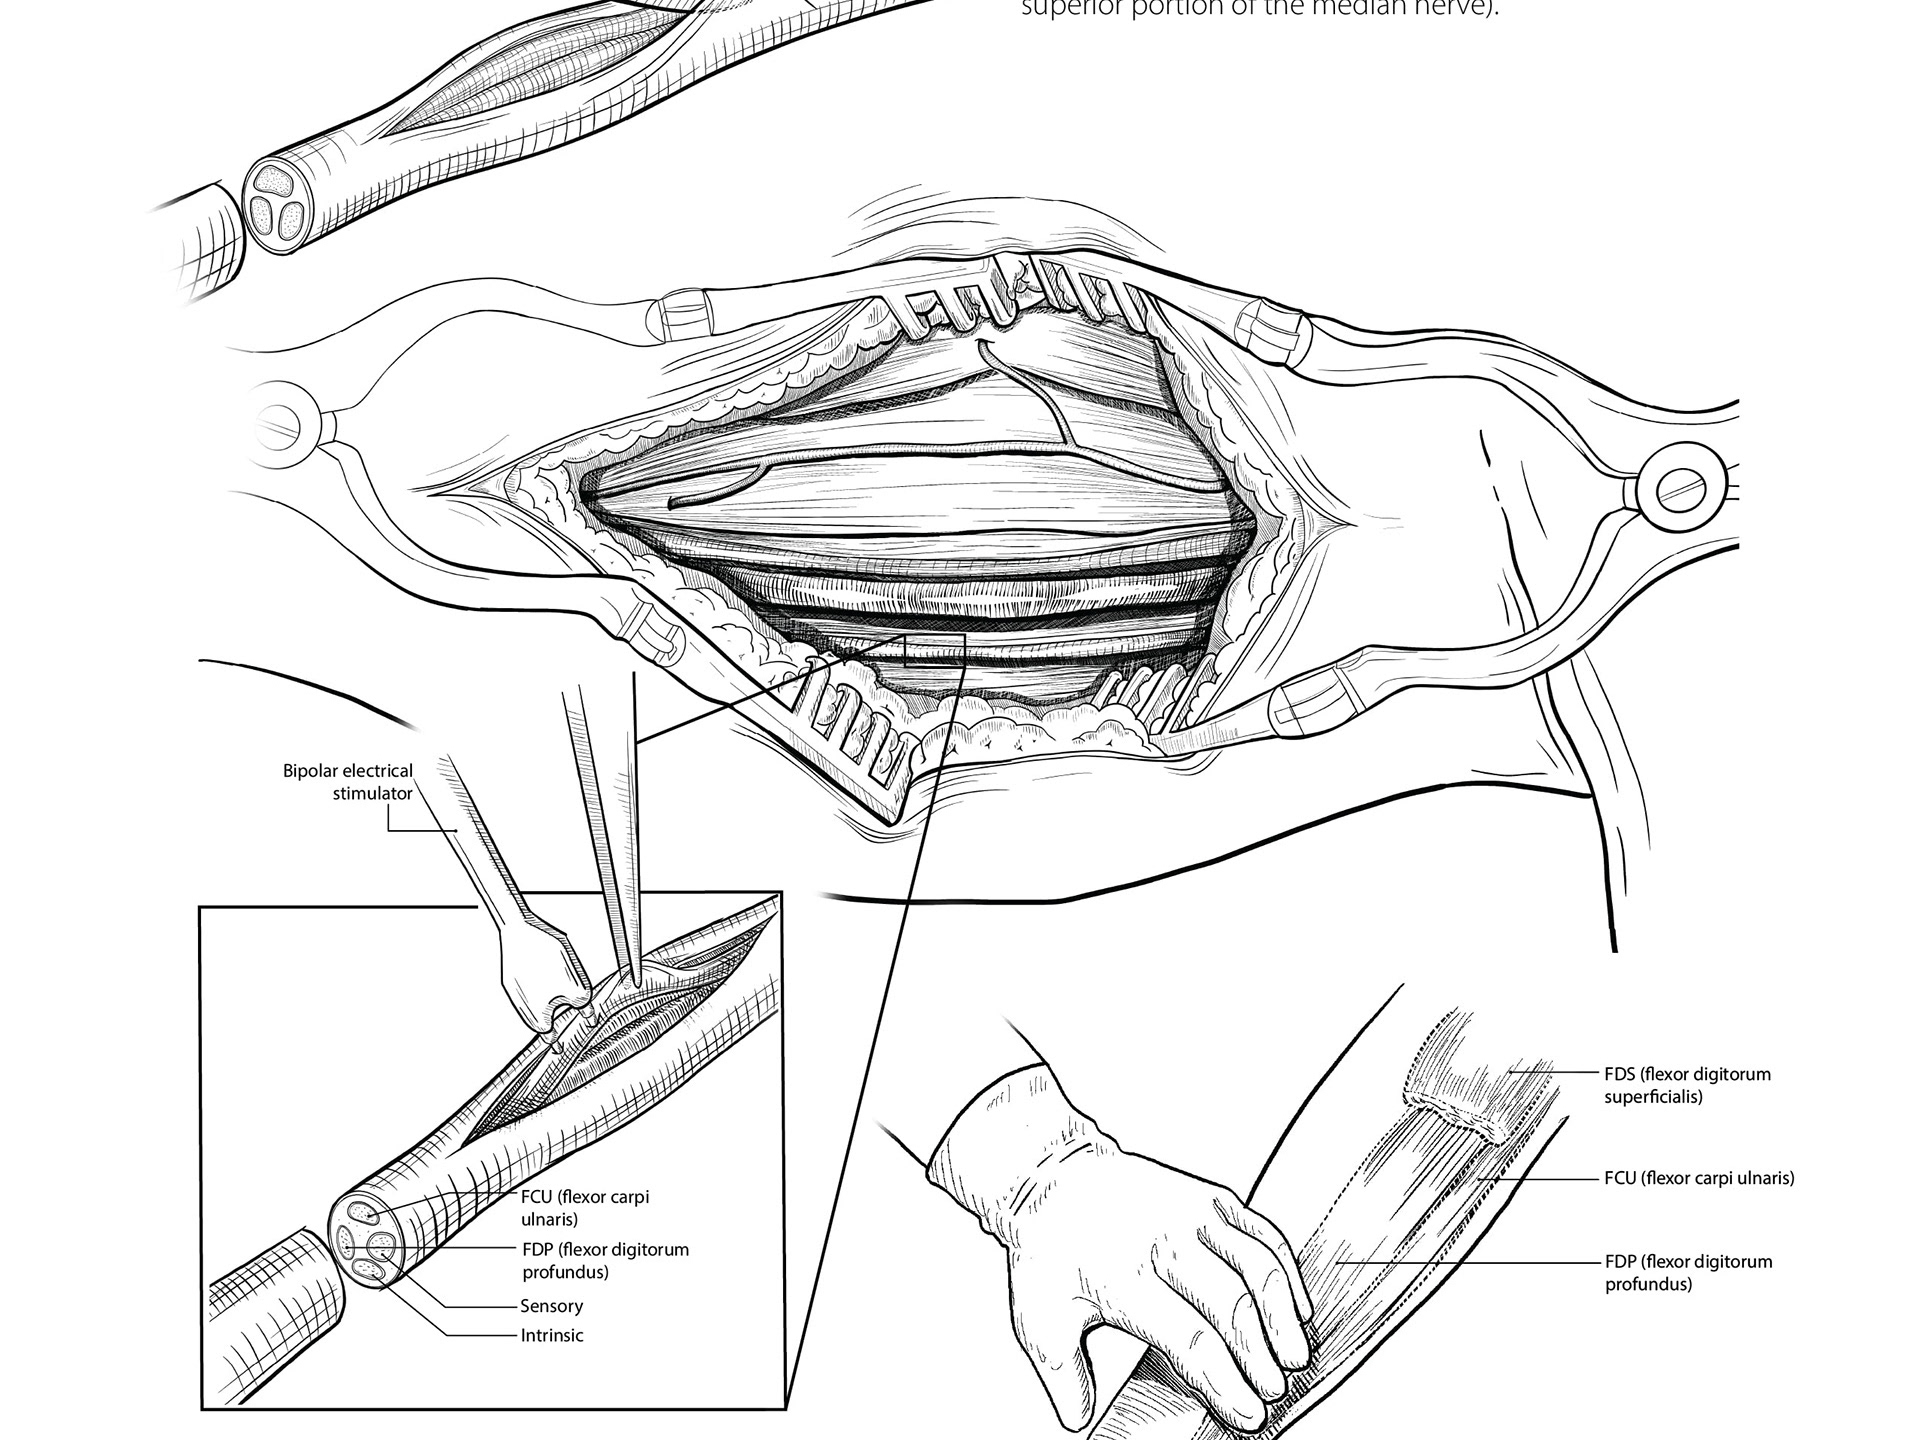

Double Fascicular Nerve Transfer

2024

Surgical Illustration | Photoshop, Illustrator, Procreate | Client: Michael Corrin